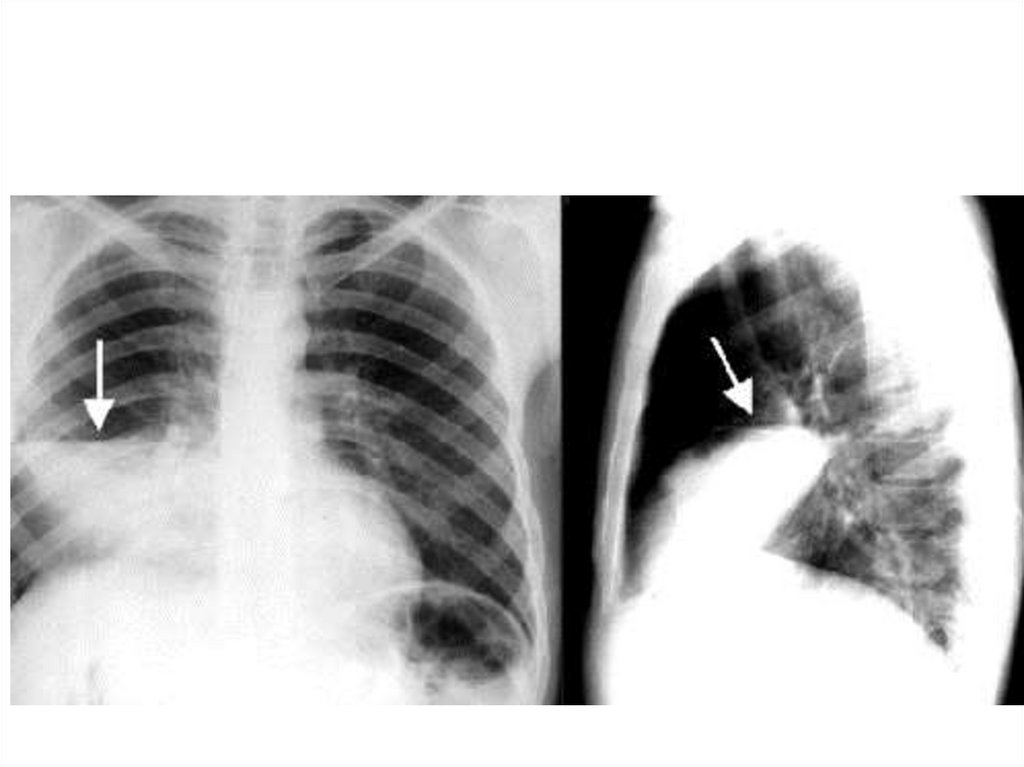

Ателектаз